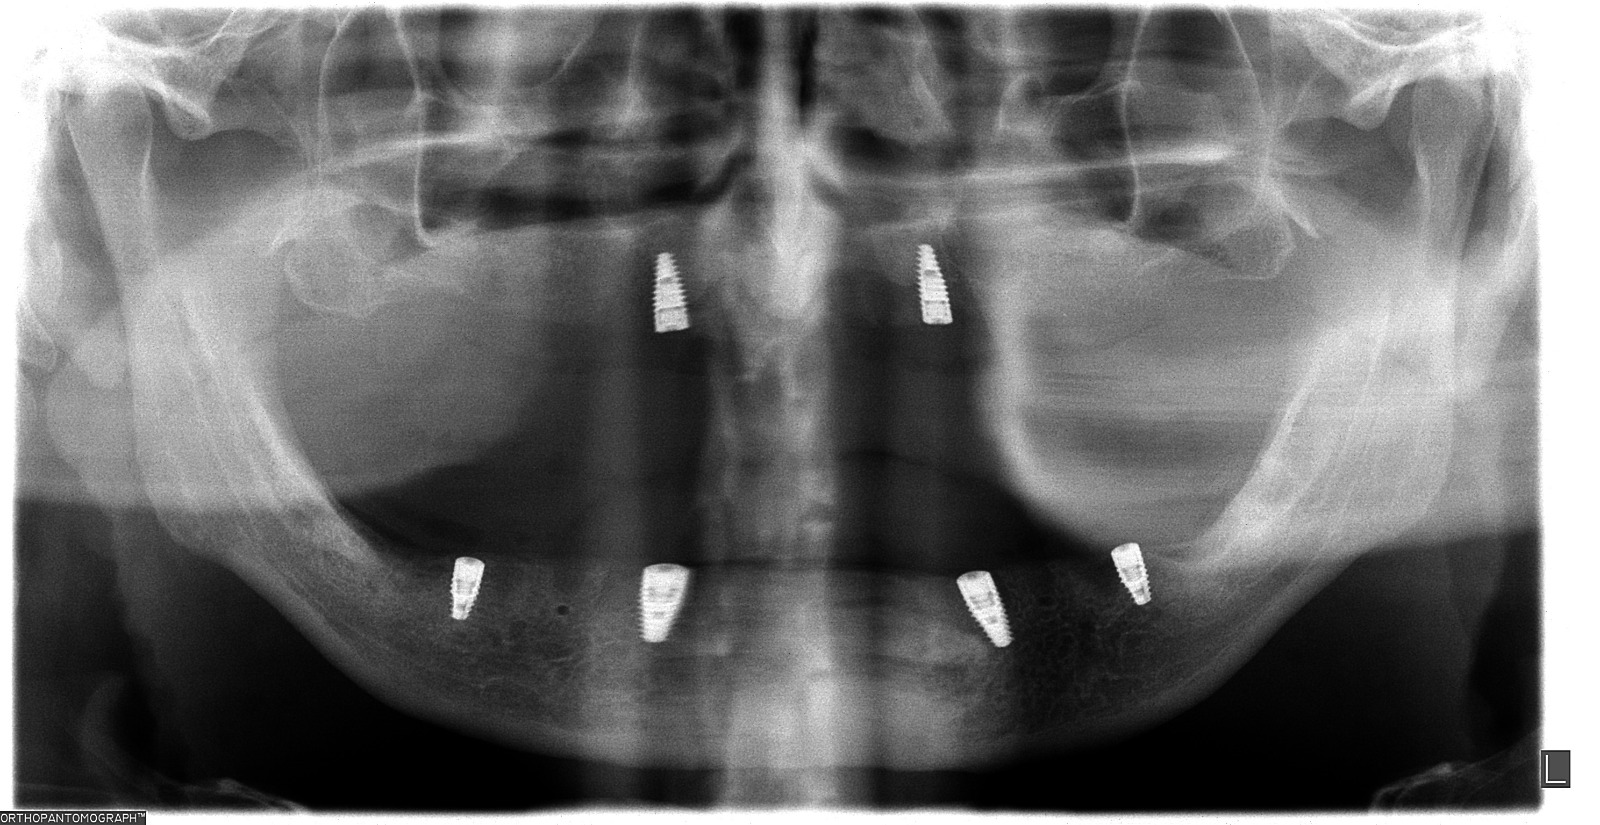

Seguimiento de Caso

Planificación de Implantes: Precisión milimétrica

Máxima precisión en implantes dentales: Planificación con tecnología 3D

Planificación digital de implantes: La tecnología al servicio de tu sonrisa